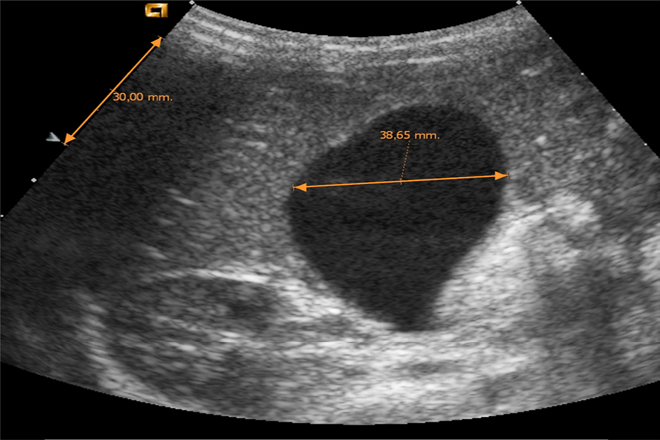

Acompañado de USG:

Engrosamiento de pared, edema importante perivesicular, colecciones perivesiculares e imágenes heterogéneas intravesiculares.